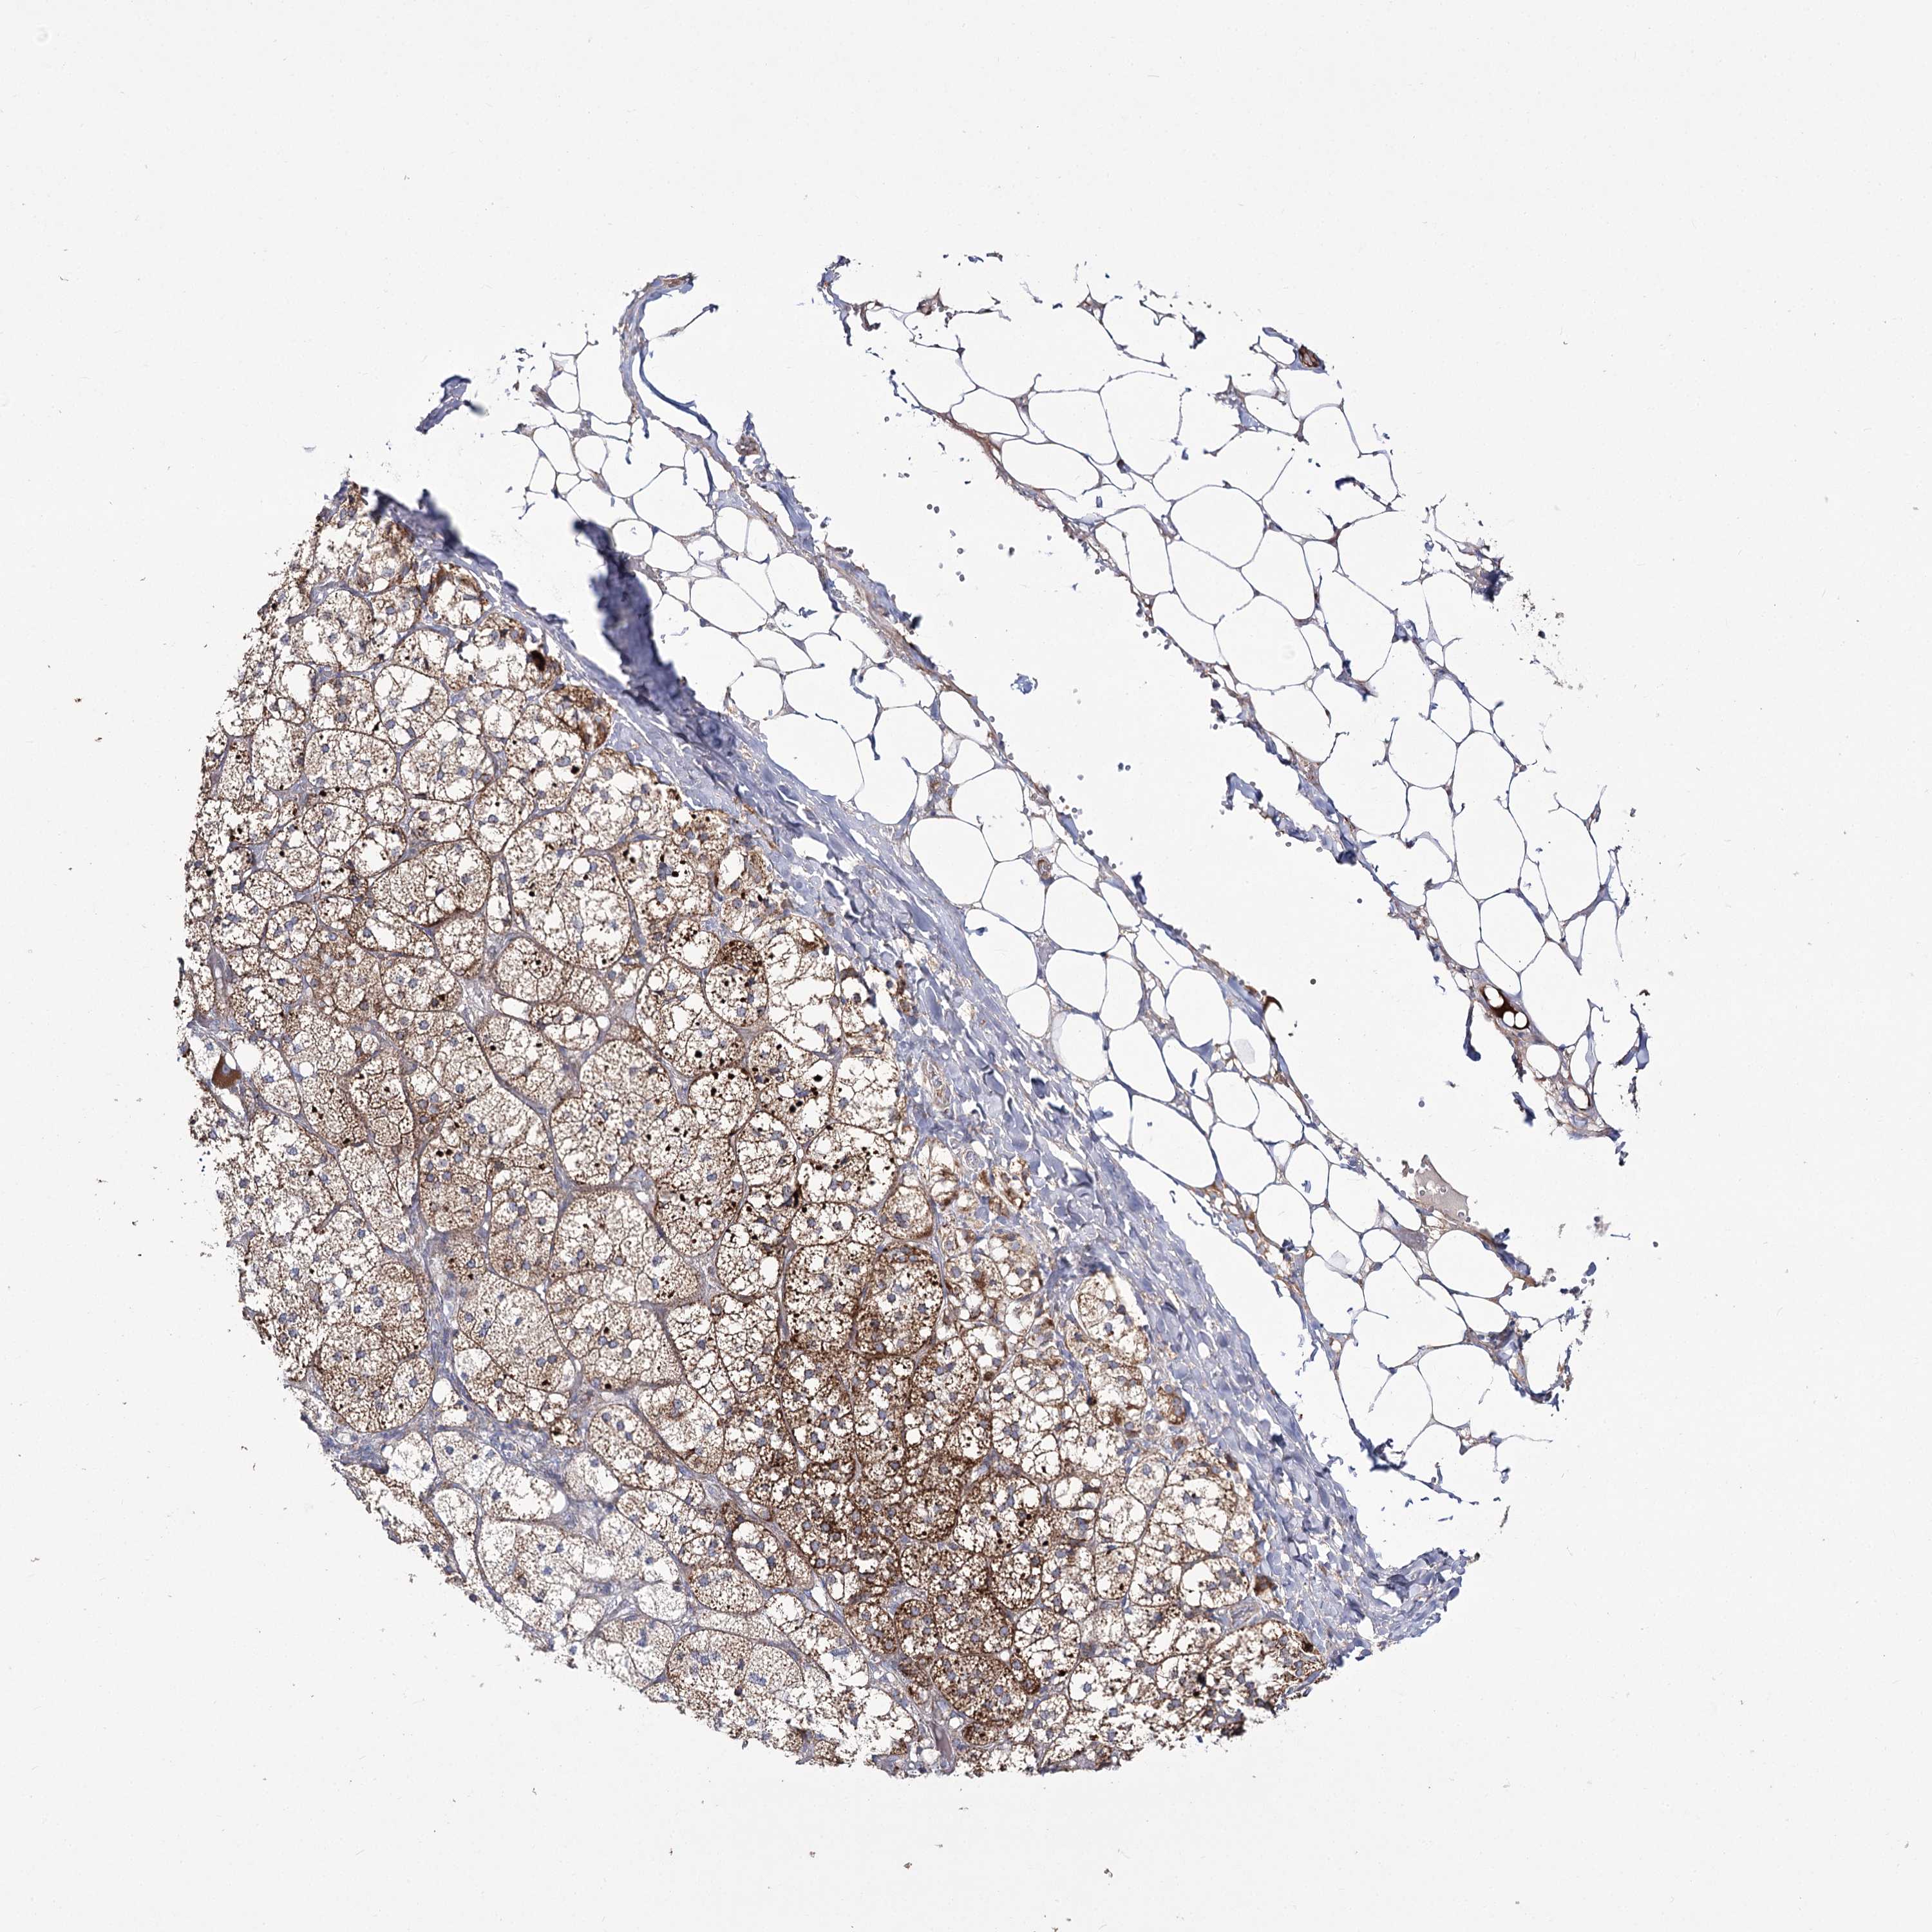

TISSUE PRIMARY DATA ADRENAL GLAND Show tissue menu

ADRENAL GLAND - Antibody stainingi

Antibody staining in the annotated cell types in the current human tissue is reported as not detected, low, medium, or high, based on conventional immunohistochemistry profiling in selected tissues. This score is based on the combination of the staining intensity and fraction of stained cells.

Each image is clickable and will lead to virtual microscopy that enables deeper exploration of all samples and also displays staining intensity scores, fraction scores and subcellular localization as well as patient and tissue information for each sample.

Antibody HPA038366Antibody HPA038367Antibody HPA061492

Glandular cells HighMediumHigh